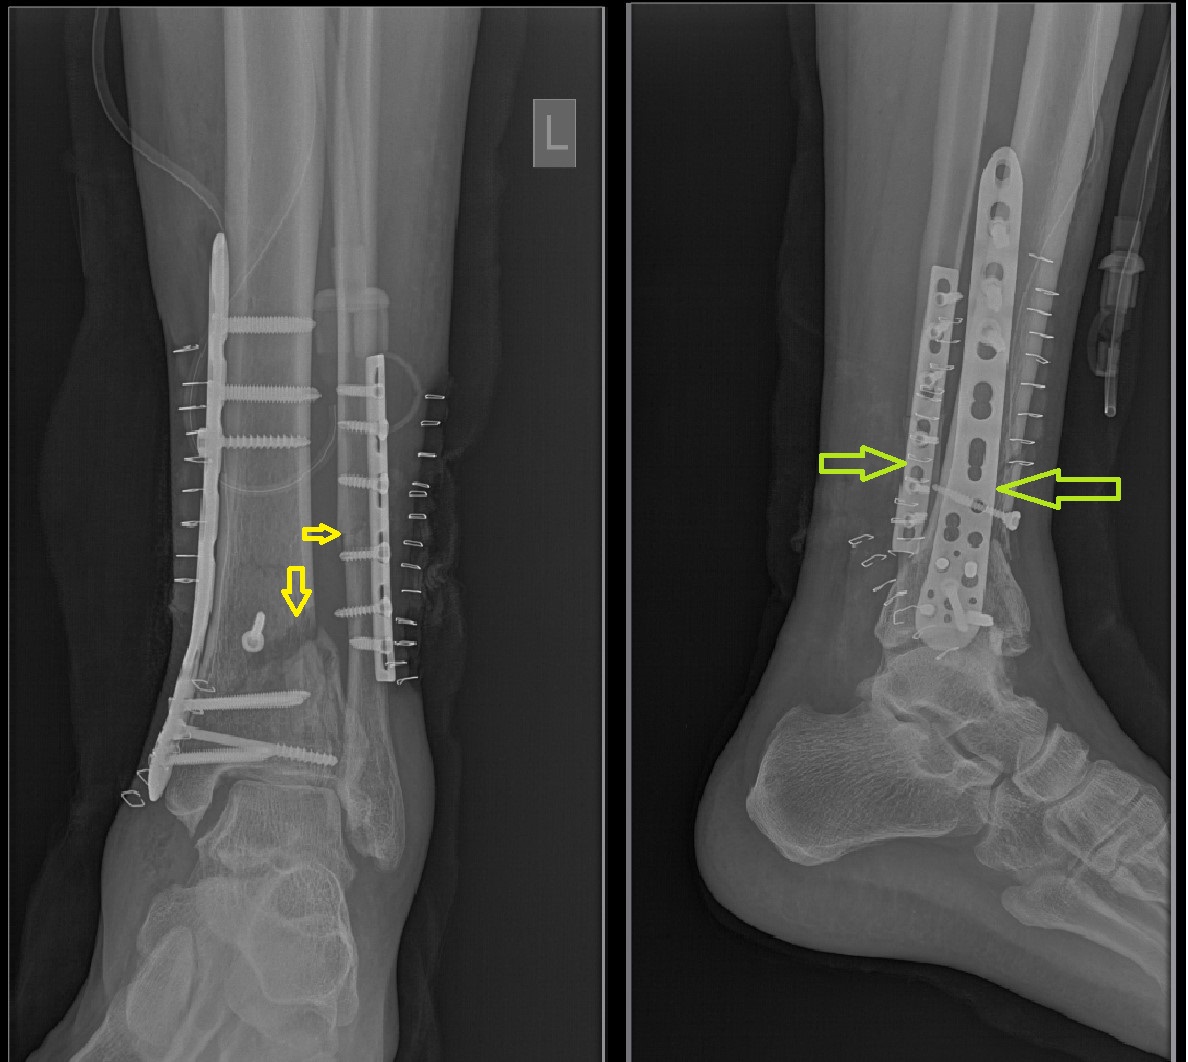

The patient underwent surgical management under spinal anaesthesia, with open reduction and internal fixation (ORIF) of the left distal fibula. Postoperative radiographs confirmed satisfactory anatomical alignment of fracture fragments with appropriate implant placement (Figure 1). The procedure was well tolerated, and the immediate postoperative period was uneventful. Wound evaluations were performed on postoperative days (POD) 3, 6, and 8. The patient received intravenous ceftriaxone 1 g twice daily, metronidazole 500mg (in 100 mL) thrice daily, and gentamicin 80 mg twice daily for five days postoperatively. Antibiotics were then discontinued. However, by POD 8, the surgical site showed signs of inflammation, including erythema, swelling, and seropurulent discharge. Considering the purulent nature of the wound and the patient’s comorbid diabetes, blood cultures were obtained to rule out systemic involvement. The negative blood culture results indicated a localized infection. A deep pus sample was collected aseptically from within the wound cavity using sterile aspiration, avoiding superficial contamination, and sent for microbiological culture and antibiotic susceptibility testing. However, we appreciate that additional confirmation of the pathogen might have been obtained if multiple intraoperative deep tissue samples had been taken during wound debridement and musculocutaneous flap coverage.

Figure 1. Anteroposterior and lateral radiographs of the left ankle demonstrating a comminuted fracture of the distal one-third shafts of the tibia and fibula, along with the postoperative status following open reduction and internal fixation (ORIF) of the distal fibula, showing satisfactory anatomical alignment and proper implant placement.